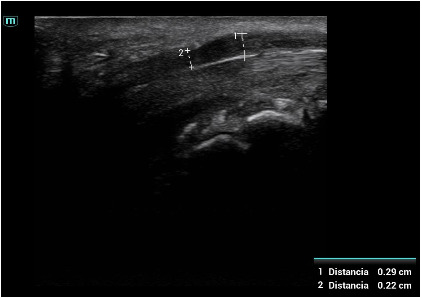

Descripción de los hallazgos ecográficos y las imágenes más relevantes para la resolución del caso

Signos de compresión del nervio mediano: área del nervio mediano 0,11 cc (> 9 patológico) con imagen en reloj de arena en la entrada del túnel del carpo.